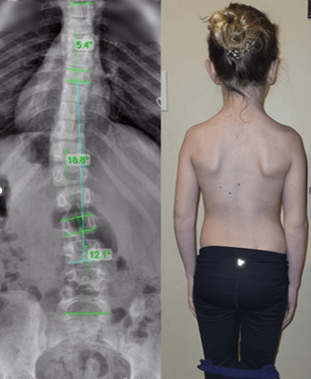

برای اندازهگیری شدت اسکولیوز زاویه کاب (Cobb Angle) را محاسبه میکنند. در این روش دو خط از شروع و پایان انحراف با همان زاویه میکشند و سپس آن دو خط را بهوسیله دو خط قائم دیگر به یکدیگر وصل میکنند. زاویهای که میان خطوط جدید شکل میگیرد، نشاندهنده میزان شدت انحراف است. در موارد بسیار خفیف، به دلیل زاویه کم، حتی ممکن است که تغییرات ظاهری در کمر و ستون فقرات مشاهده نشود، اما در موارد شدید علائمی مانند عدم تقارن شانهها یا لگن و همچنین برجستگی کتف در یک سمت مشاهده میشود.

- تصویربرداری

پس از اینکه اسکولیوز تشخیص داده شد، پزشک برای اندازهگیری دقیق میزان انحراف ستون فقرات درخواست تصویربرداری میکند. تصاویر رادیوگرافی به وضوح انحراف ستون فقرات را نمایش میدهد. پزشک از این طریق میتواند بررسی کند که ستون فقرات چقدر منحرف شده است. این تصویر معمولاً از دو جهت گرفته میشود: یکی از جلو (پروب به جلو) و دیگری از کنار (پروب به پهلو) تا انحراف در هر دو بعد مورد بررسی قرار گیرد.

- بررسی میزان انحراف

پس از گرفتن تصویر، پزشک میزان انحراف ستون فقرات را با دقت اندازهگیری میکند. این اندازهگیریها معمولاً با استفاده از خطوط مرجع انجام میشود که پزشک روی عکس رادیوگرافی رسم میکند. این خطوط به طور خاص در نقاطی از ستون فقرات که انحراف وجود دارد، کشیده میشوند. پزشک این خطوط را بررسی میکند تا زاویهای که انحراف ایجاد کرده را اندازهگیری کرده و میزان شدت انحراف را تعیین کند.